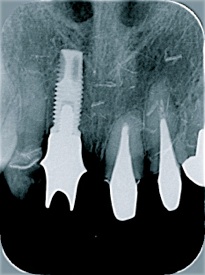

右の前歯が一本ありません。

最初の仮歯の状態です。

症例2

前歯の場合笑った時の歯の

見え方、歯茎の見え方も注意してインプラントの位置を考え

なければなりません。

他の残っているご自分の歯に

形を合わせないと審美的に

満足はえられません。